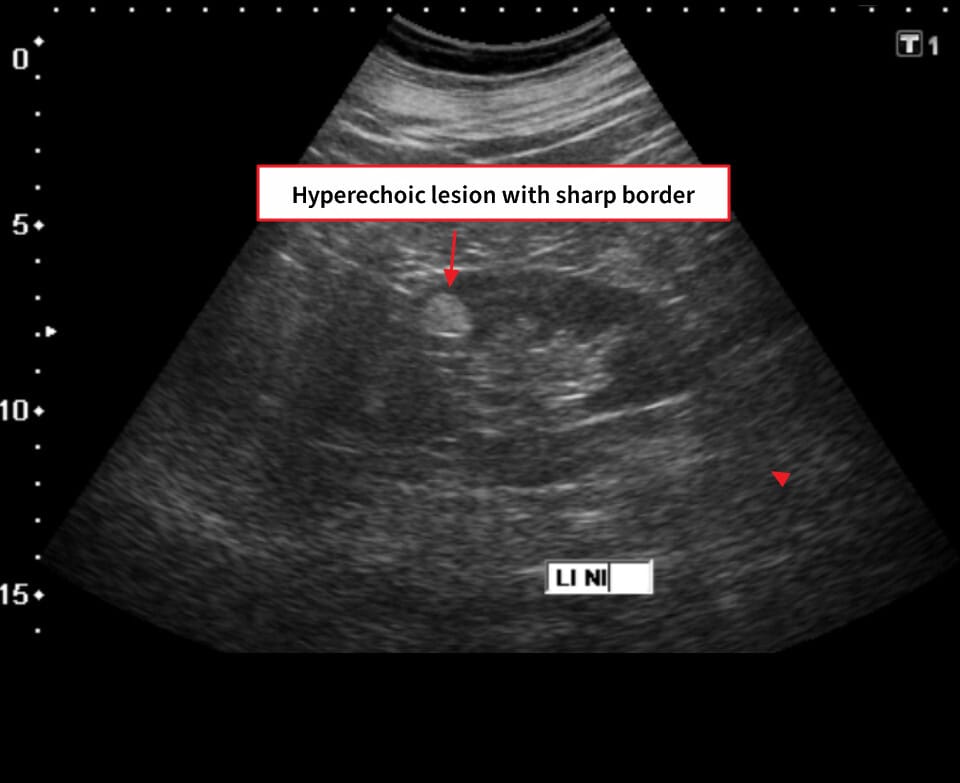

[진단]

– CT/MRI에서 지방 성분(−HU) 확인

Schubert R, Renal angiomyolipoma. Case study, Radiopaedia.org (Accessed on 19 May 2025) https://doi.org/10.53347/rID-16842